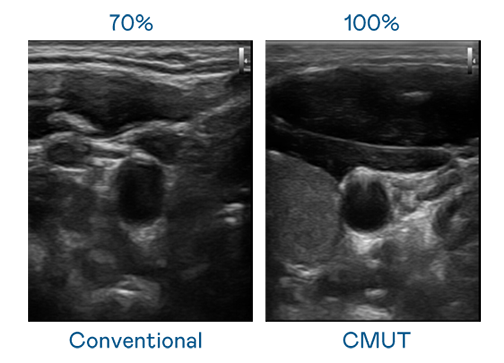

CMUT 技术是一种用电容式微机电元件来产生超音波讯号的技术。与传统 PZT 压电式技术相比,CMUT 频宽增加 30%,更宽频的超音波讯号让影像解析度大幅提升,是实现高影像品质医疗超音波扫描、促进精准医疗发展的关键技术。

超音波影像的解析度高低,首先取决于探头能发出的讯号频宽。GGPoker CMUT 可提供高清晰的超音波讯号,提供高频宽、高灵敏度、影像纹理细节更高的超音波影像,协助医护人员缩短影像判读时间及利用精准的医疗影像进行诊断。